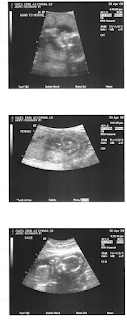

Healthy kidneys, good looking spinal cord, beating heart, well attached umbilical cord... 10.5 inches long, 14 ounces, due in mid-September.

If you can't see a baby in these photos, you're not alone, it took Luke awhile to "get" them too. (and neither of us can figure out the face)